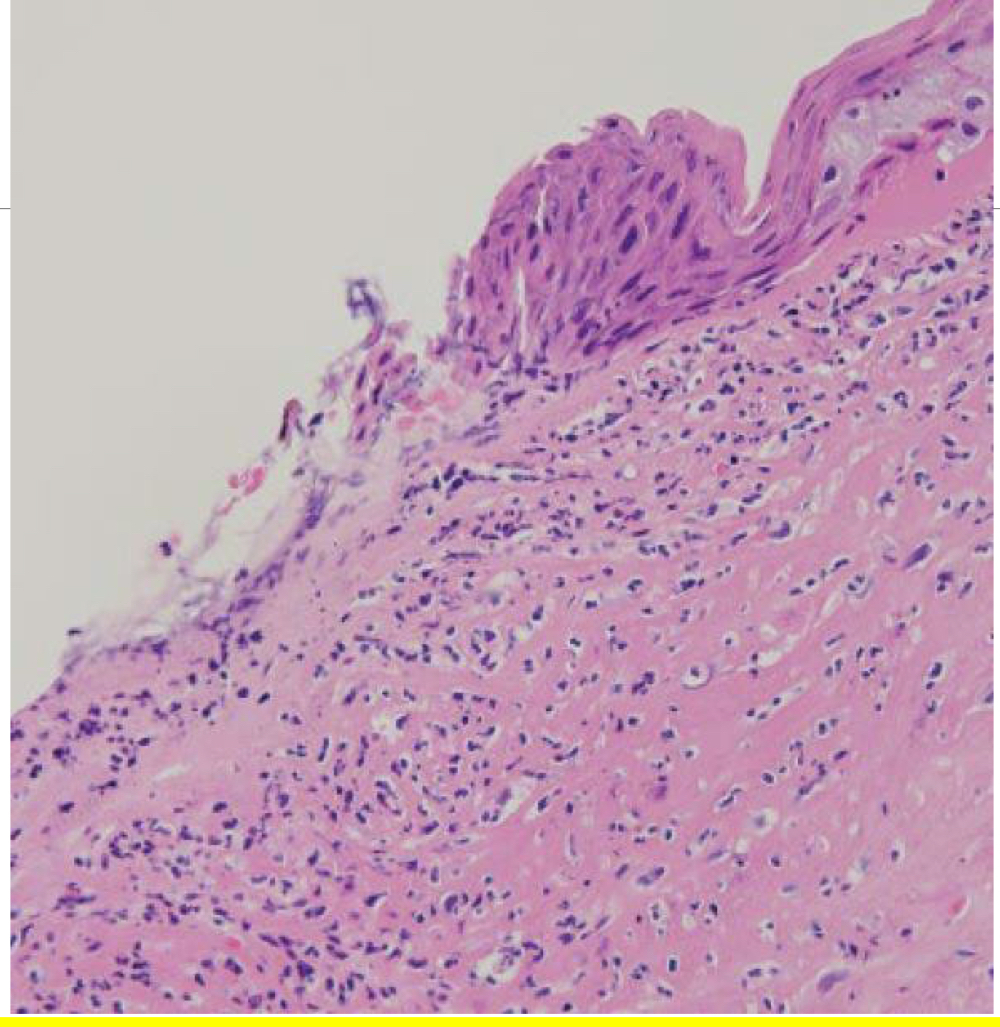

What is indicative of chronic keratitis?

lymphoplasmacytic inflammation leads to epidermalization (eye becomes "skin-like") ---> acanthosis, melanosis, vascularization, stromal scarring (fibrosis)